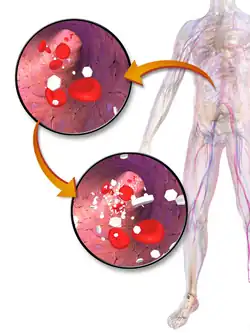

| Artist's depiction of hyperglycemia. White hexagons in the image represent glucose molecules, which are increased in the lower image. | |